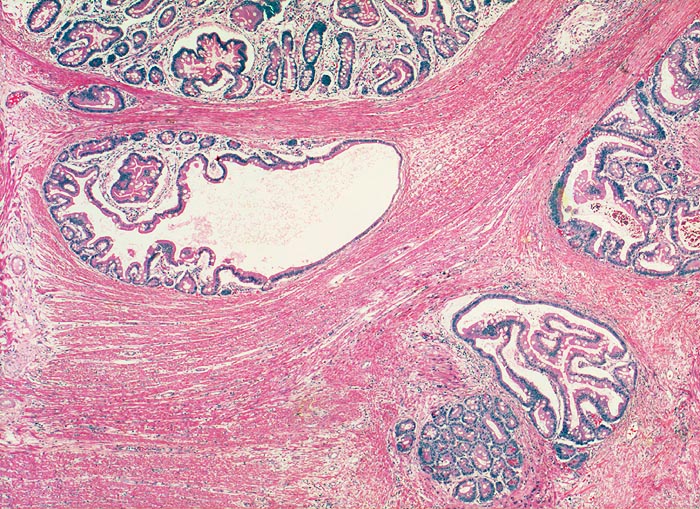

PathoPic – image database / PathoPic ID 3056 - Peutz Jegher Polyp mit Pseudoinvasion

Peutz Jegher Polyp mit Pseudoinvasion

Jejunum

Benigne, in die Muscularis propria verlagerte Drüsenschläuche an der Polypenbasis imitieren ein invasives Karzinom. Die fehlenden Epithelatypien und der normale Epithelaufbau mit begleitender Lamina propria ermöglichen die Unterscheidung von einem Karzinom.

Breitbasiger Polyp von 3cm Durchmesser.

Epithelverlagerungen in die Submukosa und Muscularis propria kommen nur in Dünndarmpolypen vor.